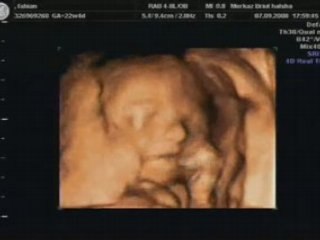

échographie du 6ème mois (3)

Uploaded: 2007-07-19